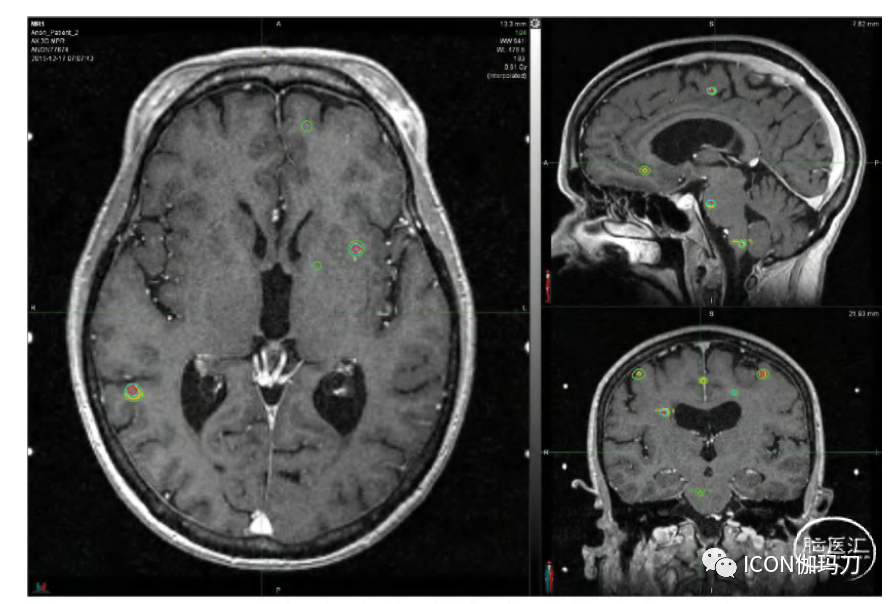

对接受大数目肿瘤治疗的患者的脑部剂量学进行评估的系列研究显示,相对较低的平均全脑剂量和相对较低的正常结构的受照剂量,尽管这些研究之间的比较有些困难,因为一些研究报告了在一个SRS疗程中治疗较大数目的肿瘤,而其他研究报告了随着时间的推移,连续SRS治疗的累积肿瘤数目和正常结构受照的累积剂量。然而,即使在转移瘤数目最多的研究系列中,平均全脑剂量通常也较低,如图32.2所示。NYU系列治疗的112个肿瘤的最大平均全脑剂量为10Gy。

图32.2我们纽约大学(NYU)研究中典型患者的T1 MPR增强MRI和全脑DVH,4次疗程共治疗了31个肿瘤。在所有疗程的剂量相加后,12Gy等剂量线(绿色)的重叠很小。虽然肿瘤数目众多,但单个肿瘤体积较小,累积平均全脑剂量为1.5 Gy。该影像用于计划第四次疗程。患者最初出现两个肿瘤,接受20Gy边缘剂量的治疗。